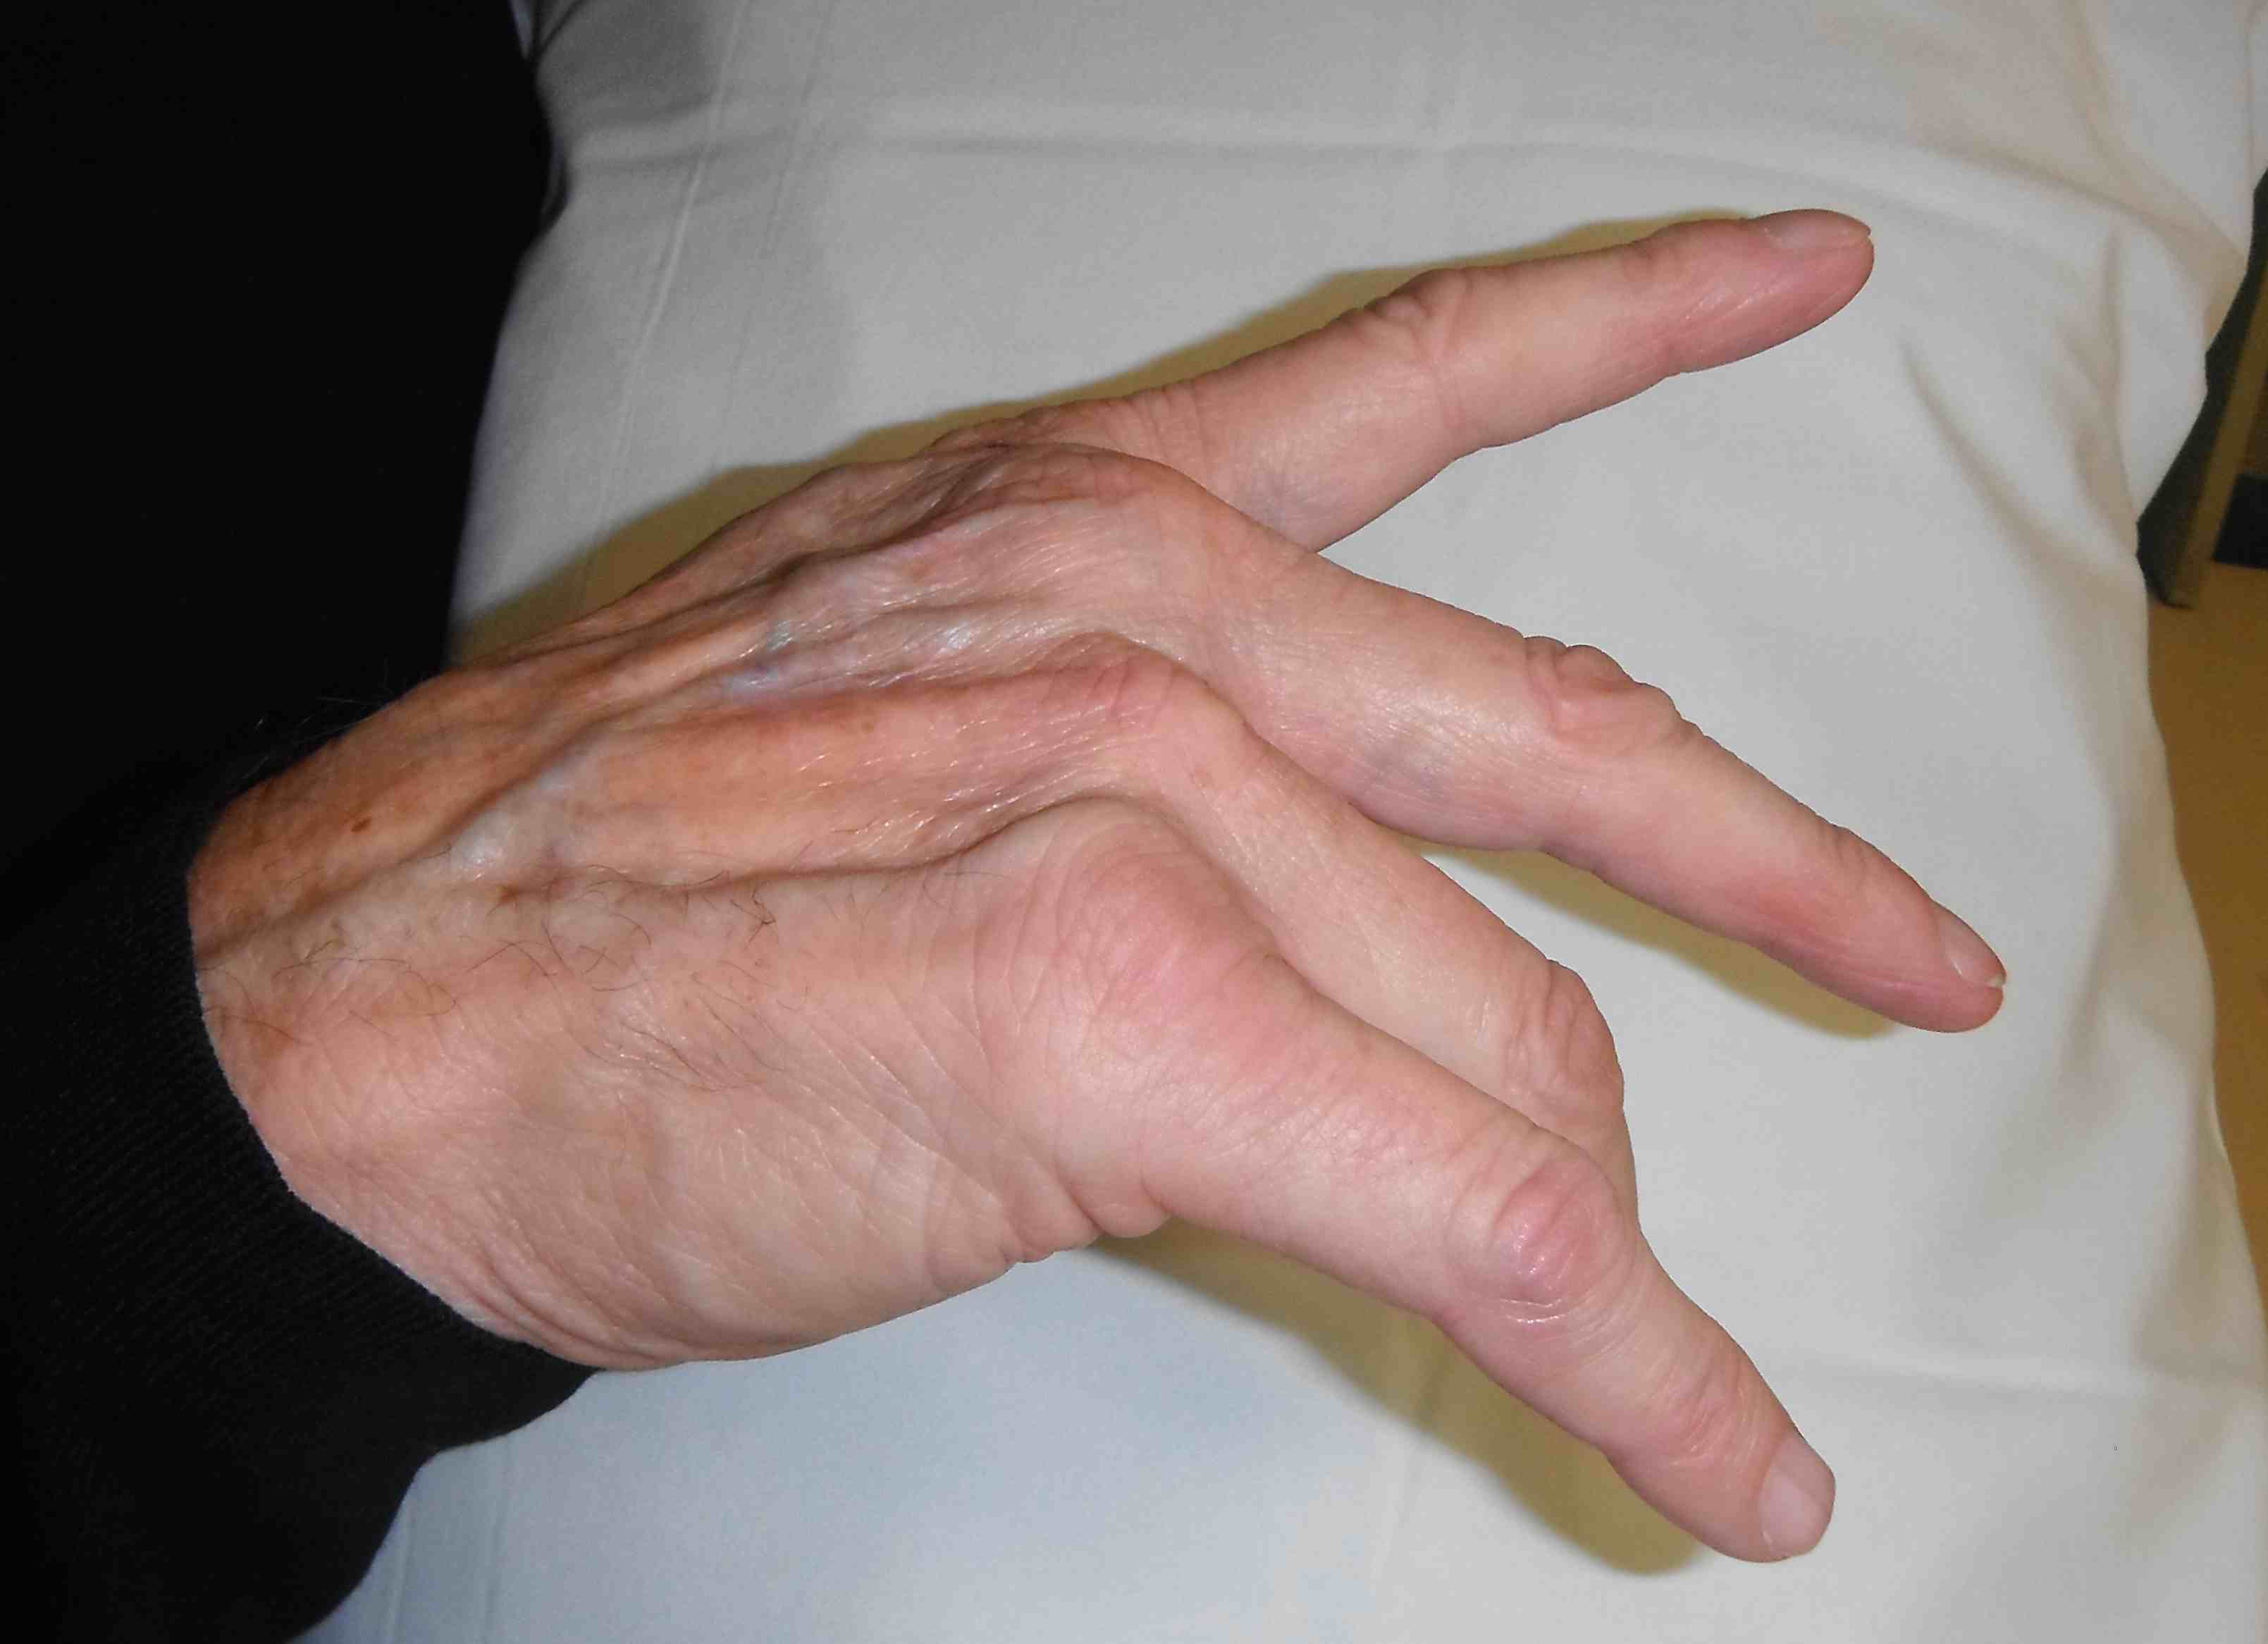

Wrist commonly affected in RA

1. Synovitis

Ulnar side

- develop caput ulna

- ulnar becomes prominent because carpus is falling away from it

- carpus volar translated & supinated

3. Carpal Collapse